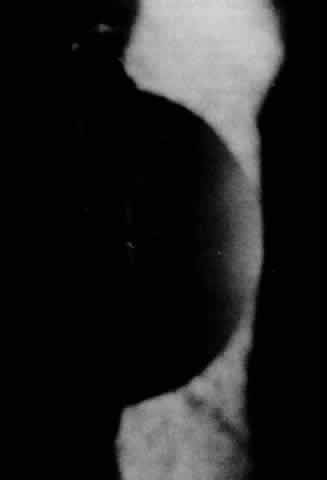

The literature contains many descriptions and names for posterior polymorphous dystrophy owing to the variety of clinical findings.189–193 Koeppe is credited with the first description in 1916 of six patients with congenital pits on the posterior surface of the cornea. Subsequently, multiple clinical and histopathologic reports described this generally bilateral, asymmetric, or even unilateral dystrophy. Although vesicles (Fig. 12) at the level of Descemet's membrane are traditionally described, clinical examination reveals a variety of opacifications of the posterior corneal layers.192

Fig. 12. Posterior polymorphous dystrophy: posterior corneal vesicles.

The age at onset is difficult to determine since patients are usually asymptomatic and the dystrophy is detected on routine examination. Visual acuity is usually normal. Clinical findings range from vesicles to geographic blisters to broad bands and sheets of grayish material in Descemet's membrane. Broad peripheral anterior synechiae extending around the angle for 60° to 120° in conjunction with secondary edema have been described.194,195 Glaucoma is present in about 15%. Elevated intraocular pressure is difficult to manage secondary to overgrowth of abnormal endothelium in the angle and over open surgical sites.